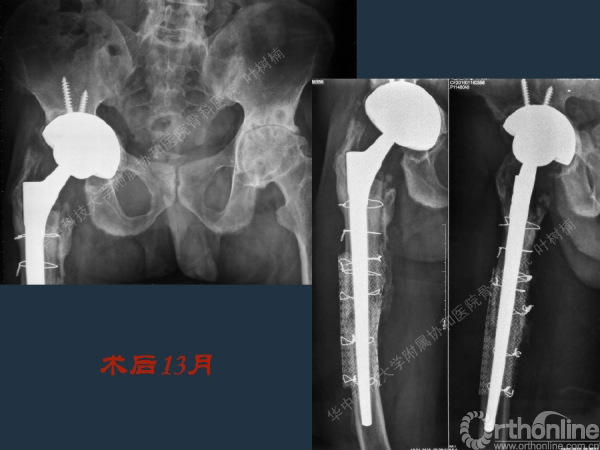

股骨侧翻修

髋臼缺损的处理